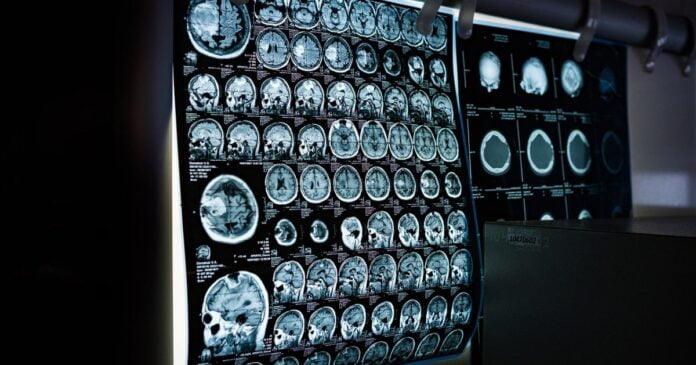

Researchers from Harvard Medical School and the McGovern Institute for Brain Research at the Massachusetts Institute of Technology based their study on structural and functional brain imaging (fMRI) data belonging to 57 newly authorized medical cannabis patients and a control group (32 participants) of non-cannabis users at baseline and after one year.

The medical cannabis cohort had received medical cannabis cards for symptoms of depression, anxiety, pain, or insomnia and were aged between 18 and 65 years. Testing at baseline and after one year included working memory, reward, and inhibitory control.